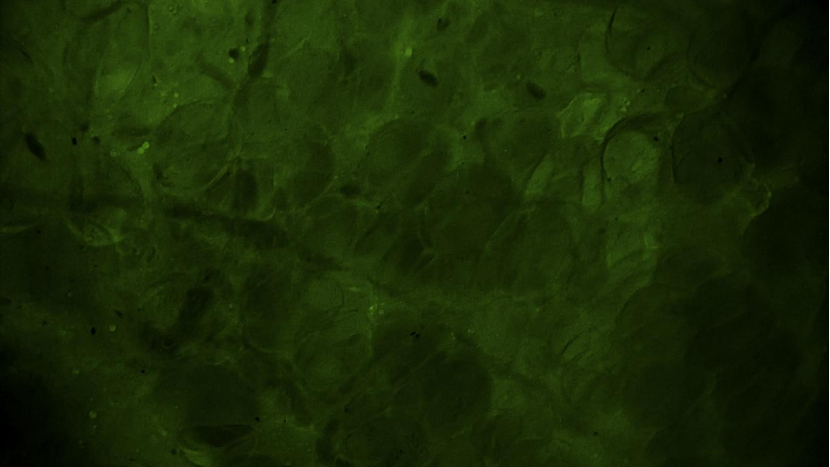

術中EndoSCell?細胞圖像如下:

脂肪組織:脂肪細胞規(guī)則透亮,分布均勻,未見腫瘤細胞